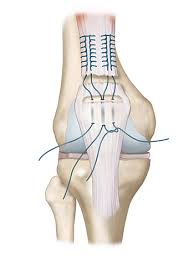

"Excellent Care for My Grandmother. We consulted Dr. Raghav Suthar

for my grandmother's knee pain and are extremely satisfied with the treatment and care

provided."

"My father had knee pain from long time. We met Dr. Raghav Suthar for

advice. He checked everything properly and explained very clearly. He gave honest

opinion. Thank you Dr. Raghav."